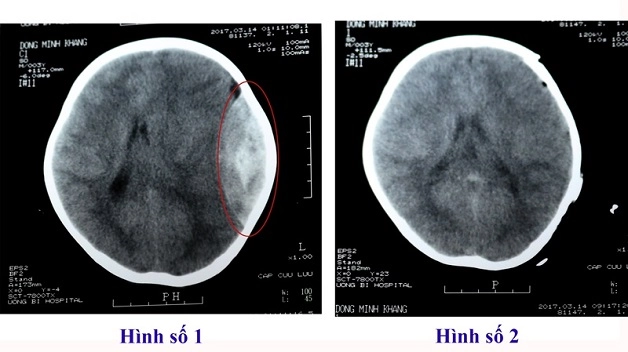

Khi chụp cắt lớp vi tính (MSCT) ra đời đã tạo là một bước đột phá mới trong chẩn đoán hình ảnh, thay vì sử dụng chụp X quang hay siêu âm như trước đây khó có thể chẩn đoán được chính xác.

Chụp cắt lớp vi tính cũng sử dụng tia X giống như chụp X quang, nhưng khi đi qua cơ thể với bộ xử lý của máy vi tính sẽ tái hiện hình ảnh tổn thương một cách rõ nét nhất, giúp bác sĩ đánh giá được mức độ, bản chất của loại tổn thương, để từ đó xây dựng phương pháp trị liệu phù hợp.

Chụp cắt lớp vi tính đa dãy ra đời với rất nhiều lớp cắt khác nhau, giúp chẩn đoán hình ảnh tủy sống và thần kinh sọ não, u não, tai biến mạch máu não, dị dạng mạch não, các bệnh lý về cột sống,… tạo một bước tiến mới trong chẩn đoán bệnh lý hệ thần kinh, đặc biệt là thần kinh trung ương (não, tủy sống).

Chụp cắt lớp vi tính đa lát cắt (MSCT đã dãy) được sử dụng rộng rãi trong chẩn đoán các bệnh lý về thần kinh và nhiều bệnh lý khác. (hình minh họa)